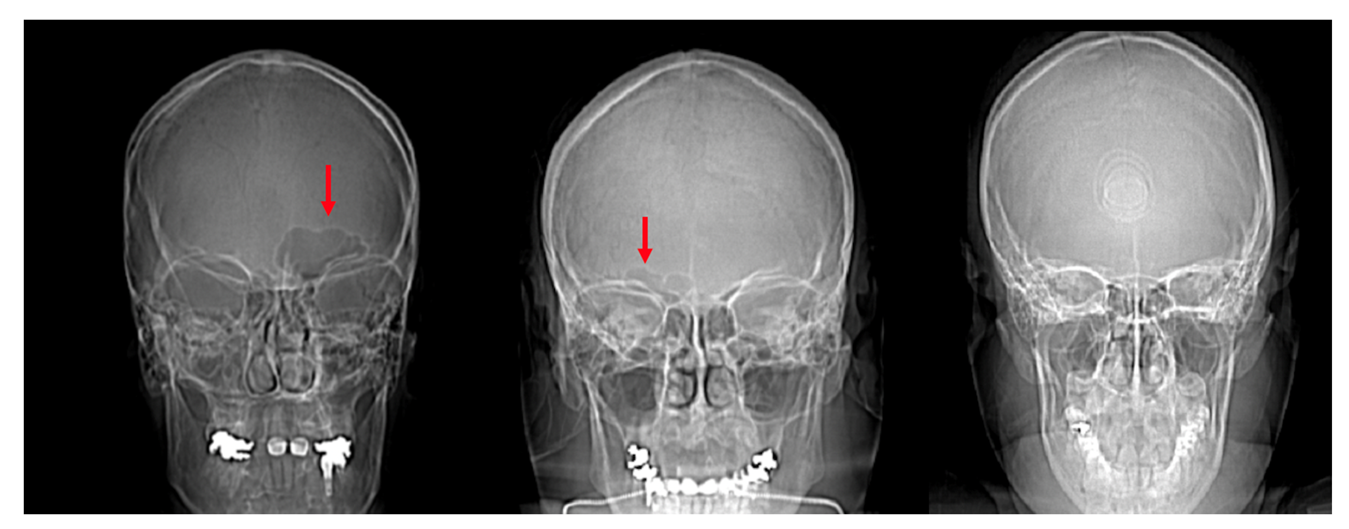

Frontal Sinus Morphological and Dimensional Variation as Seen on Computed Tomography Scans Very well made.

Frontal sinus Wikipedia Very well made.

Absent frontal sinus an uncommon radiological finding that should not be missed in CT report letter to the editor The Egyptian Journal of Otolaryngology Full Text Very well made.

The Frontal Sinus Drainage Pathway and Related Structures American Journal of Neuroradiology Very well made.

Frequency of the frontal sinus aplasia among Saudi Arabian population. A single center retrospective case review Saudi Medical Journal Very well made.